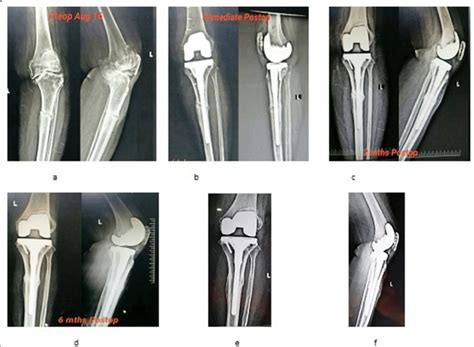

Learn how to prevent and treat them. Tenderness was found over the lateral aspect of the leg, and radiographs showed an area of calcification along the shaft of the proximal fibula. Carrying approximately 17% of your body weight and transferring it from the shin to the foot, supporting your leg, ankle and body muscles. Stress fractures are common injuries in athletes and military recruits. (a) proximal tibial stress fracture (arrow). However, when it happens it usually affects the part just below the knee called proximal tibia. A 45 year old woman with ra the resultant change in clinical outcome/course is outlined in this case report. Fractures may present as pain and tenderness over the lateral proximal fibula or as knee pain. Stress fractures of the fibula are caused by an imbalance between bone formation and bone resorption (removal). Lower end fibula fractures are common in older adults. Biomechanical studies have shown that the fibula receives between 6.4% and 16.7% of the load transmitted from the lower extremity. Rest from training and competition until the local bone tenderness is gone. Fibula fractures are a common injury to the smaller of the two bones that comprise the lower leg. The proximal fibula is the insertion. Learn how to prevent and treat them. Frontal impact at the level of the proximal tibiofibular joint may result in posterior dislocation of the fibular head. • mean age at the time of injury was 7.1.